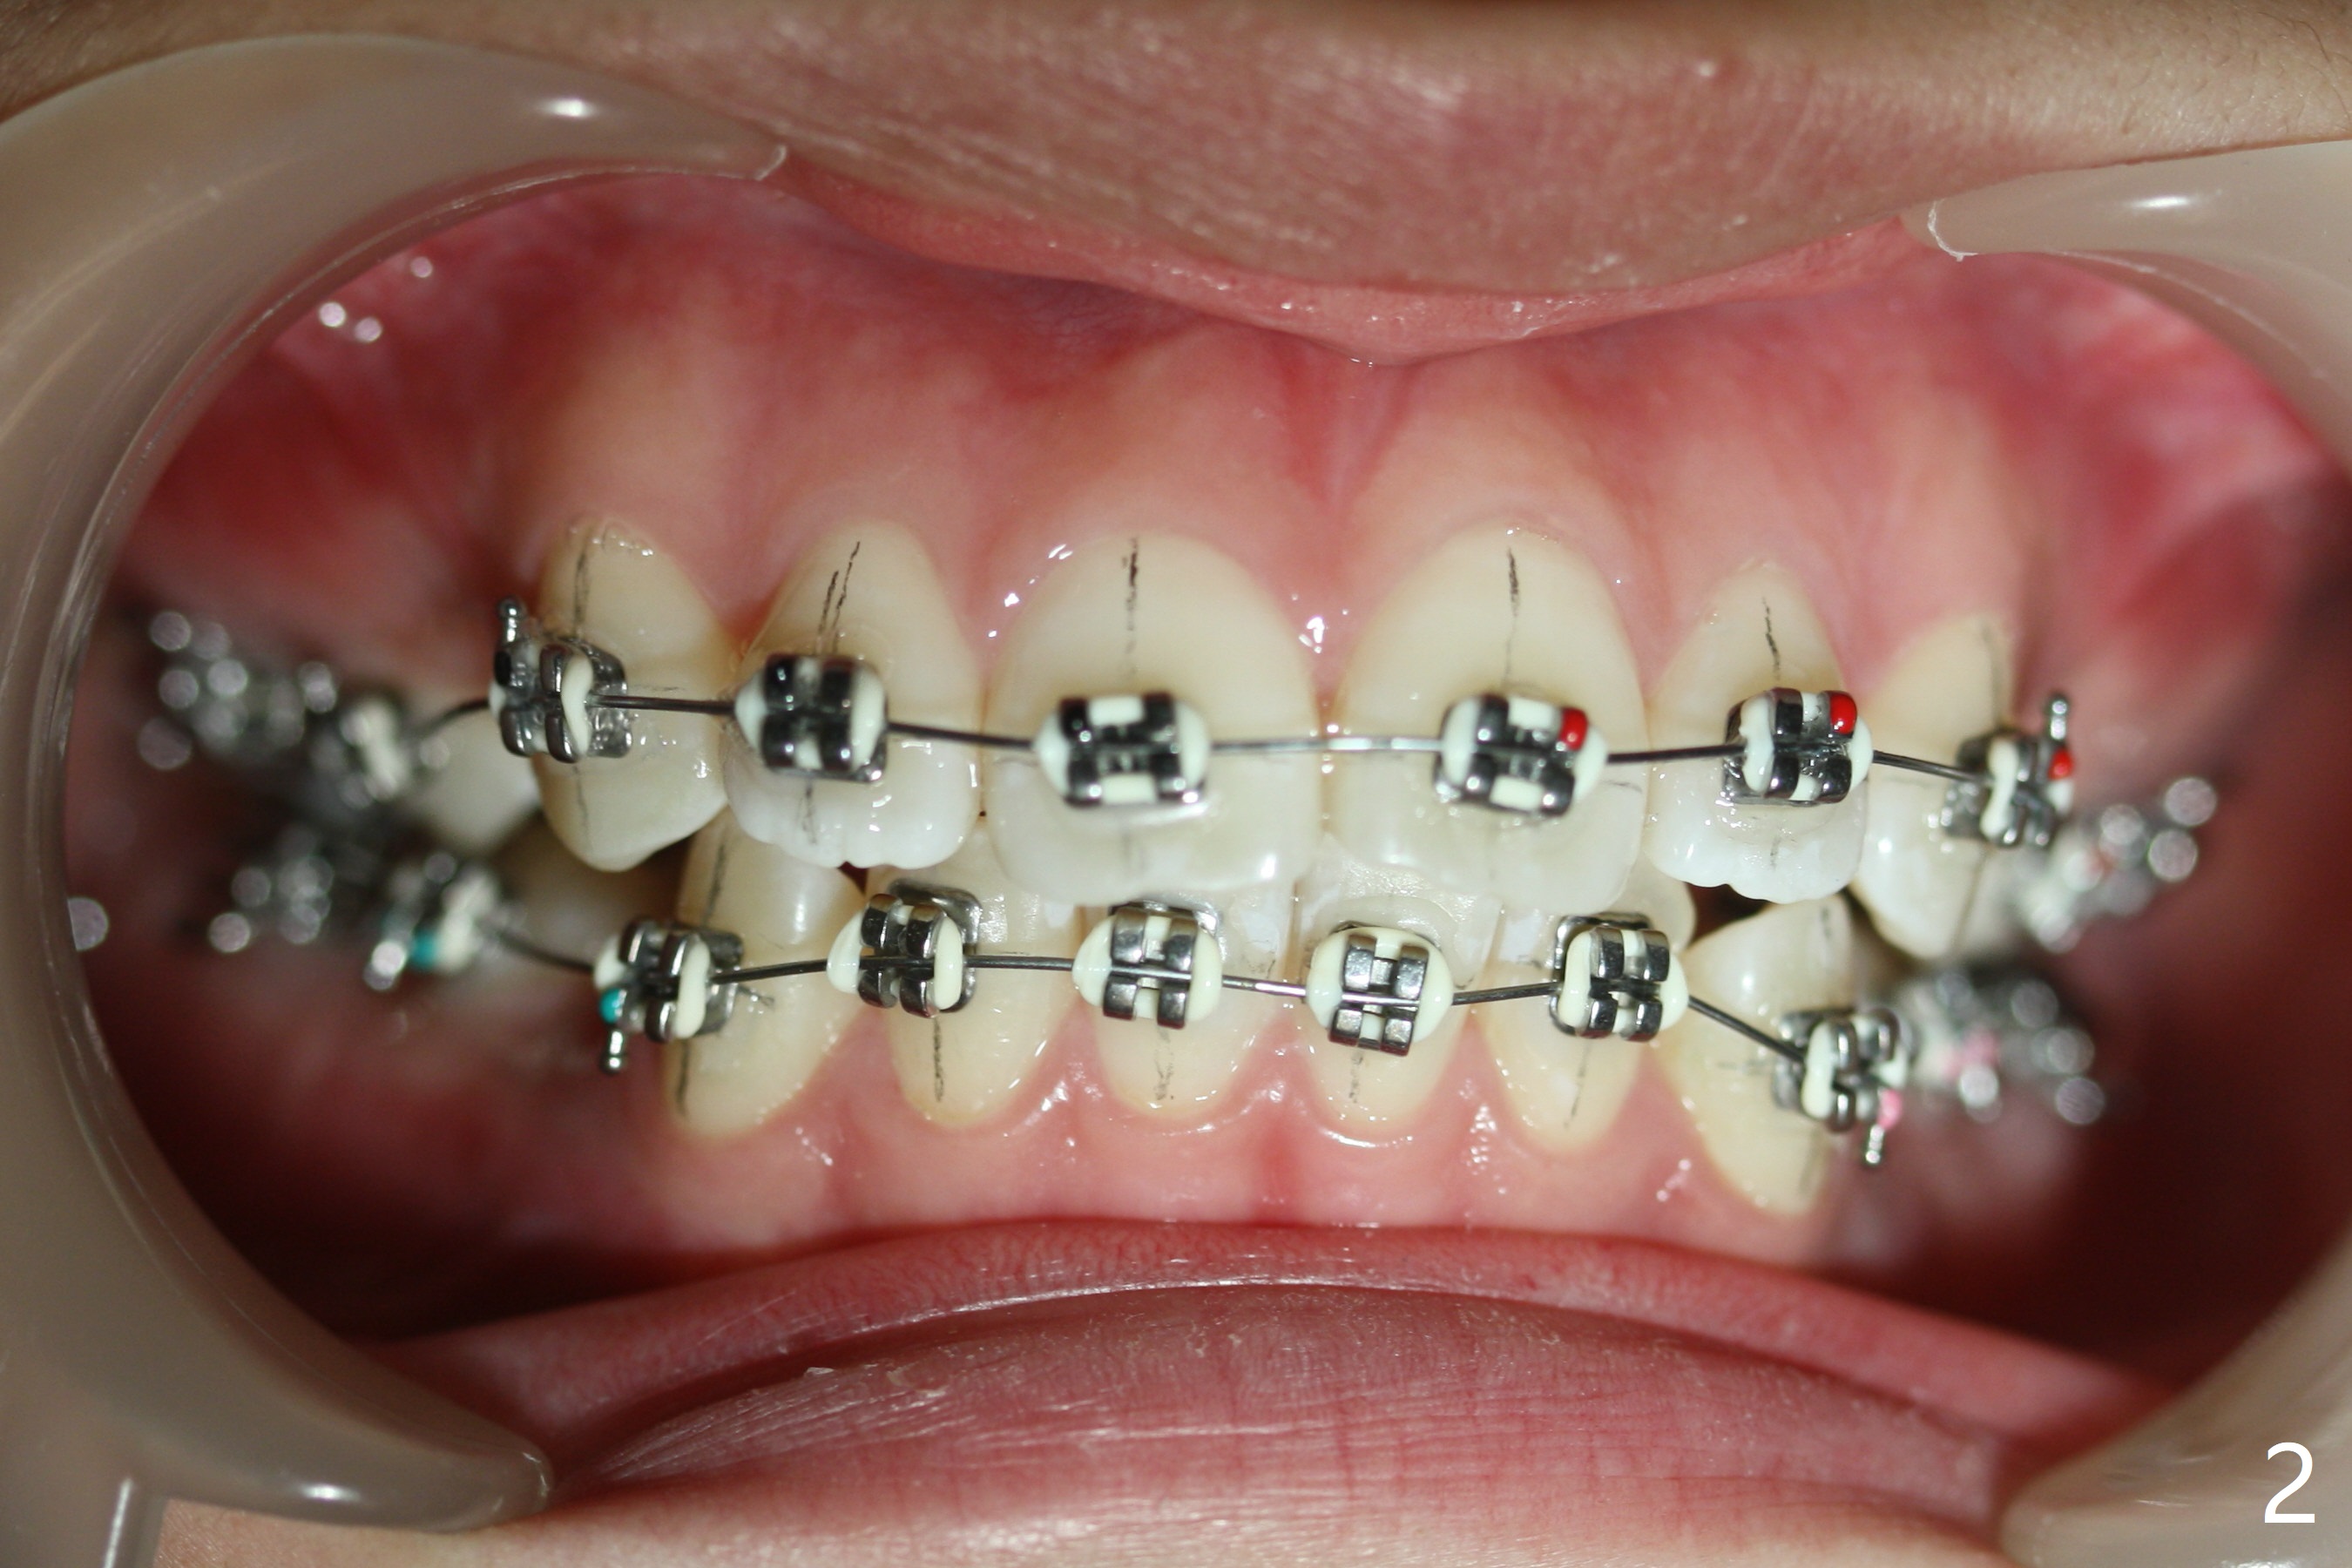

Two weeks post extraction of 4 bicuspids, brackets and bands are placed in 20 teeth (Fig.1-3, 14 niti). No bands are placed at 7s because of short crowns and tight contacts. When 16x16 wires are used, start Class II retraction. The latter is initiated with elastics when 18 ss wires are placed (Fig.4,5). U3s have been distalized with closed springs for 3 months (Fig.6,7). U2s are close to distalization 13 months post banding, 3.5 months post posted wire (Fig,8,9) with overjet (Fig.10). Class II retraction is re-initiated. When the upper incisors are retracted, the anterior overjet remains large. It appears that U6s have been retracted anterior, as indicated by the space between U6/7 (Fig.11), because of no use of U7s as anchors. Brackets are just placed with 18 niti arch wire. They will be retracted distal using the rest of the upper teeth and lower teeth (using Class II retraction) as anchor. There is root resorption of the upper anteriors 2 years 1 month post banding (Fig.12,13).